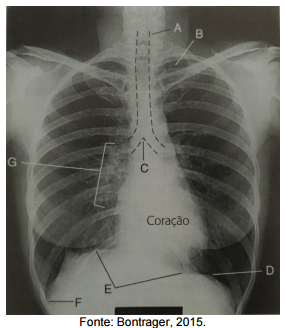

Assinale a alternativa que apresenta a correta correlação entre a indicação e a estrutura na imagem tomográfica.